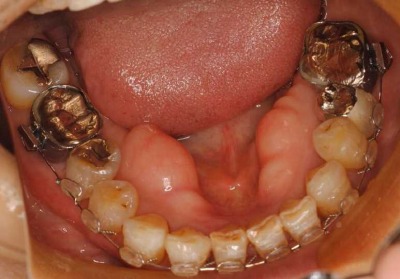

治療では、左下の奥歯に3本の矯正用インプラントを入れました。

拡大した写真です。

このインプラントを支えにして、奥歯を元の後側の位置まで引っ張りました。

左下前歯の重なりが無くなって、きれいになったので、右も新しく装置を入れてほぼきれいに一列になってきました。